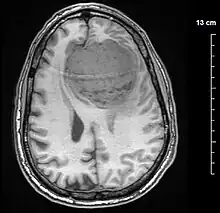

Diagnosis

Meningiomas are visualized readily with contrast CT, MRI with gadolinium,[22] and arteriography, all attributed to the fact that meningiomas are extra-axial and vascularized. CSF protein levels are usually found to be elevated when lumbar puncture is used to obtain spinal fluid. On T1-weighted contrast-enhanced MRI, they may show a typical dural tail sign absent in some rare forms of meningiomas.[17]